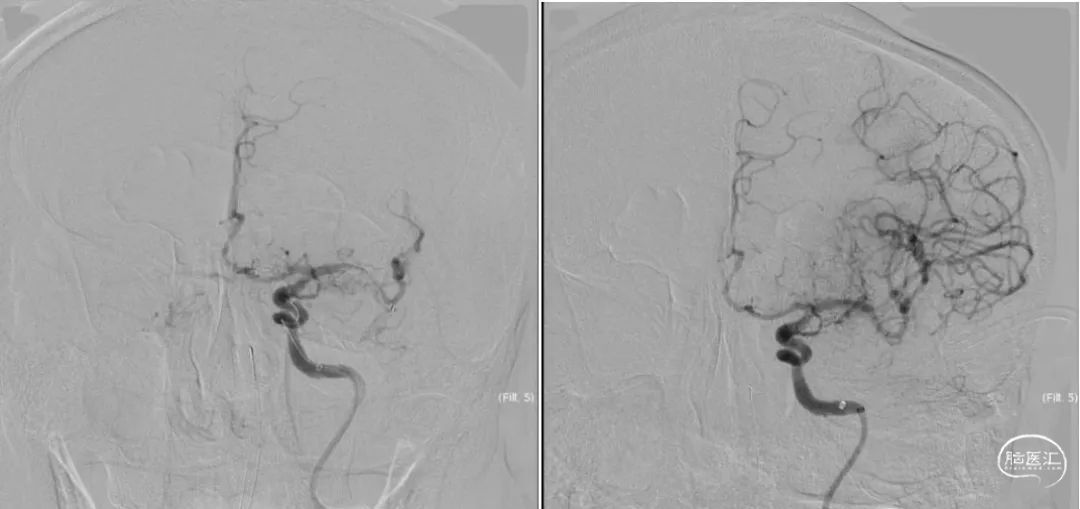

入院DSA:III型主动脉弓,后循环代偿不足,见图3,前交通动脉开放,左侧大脑前动脉通过软脑膜枝向左侧大脑中动脉供血区部分代偿,左侧颈内动脉起始部闭塞,左侧颈外动脉通过眼动脉向颈内动脉部分代偿,左侧大脑中动脉血栓形成,TICI分级0级,见图4。

图3.DSA造影:主动脉弓及左侧左侧椎动脉造影

图4.DSA造影:右侧颈内动脉正位及左侧颈内动脉侧位造影